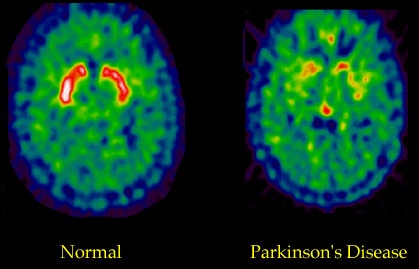

Основой же метода является вводимый в организм пациента трейсер – синтетическое вещество, содержащее радиоизотоп. Суть исследования заключается в том, что трейсер является аналогом того или иного метаболита, который используется организмом, например, захватывается специфически определенными клетками. В качестве трейсера можно использовать изотоп кислорода-15 (повышенное потребление кислорода различными областями мозга говорит о повышении их активности); 18-фтордезоксиглюкозу – аналог глюкозы (недостаточный сигнал от захваченной глюкозы может говорить о нейродегенеративных процессах в данной области); 18-фтор-ДОФА (ДОФА является предшественником дофамина, и снижение ее сигнала в области стриатума может говорить о скрытой досимптомной стадии болезни Паркинсона).